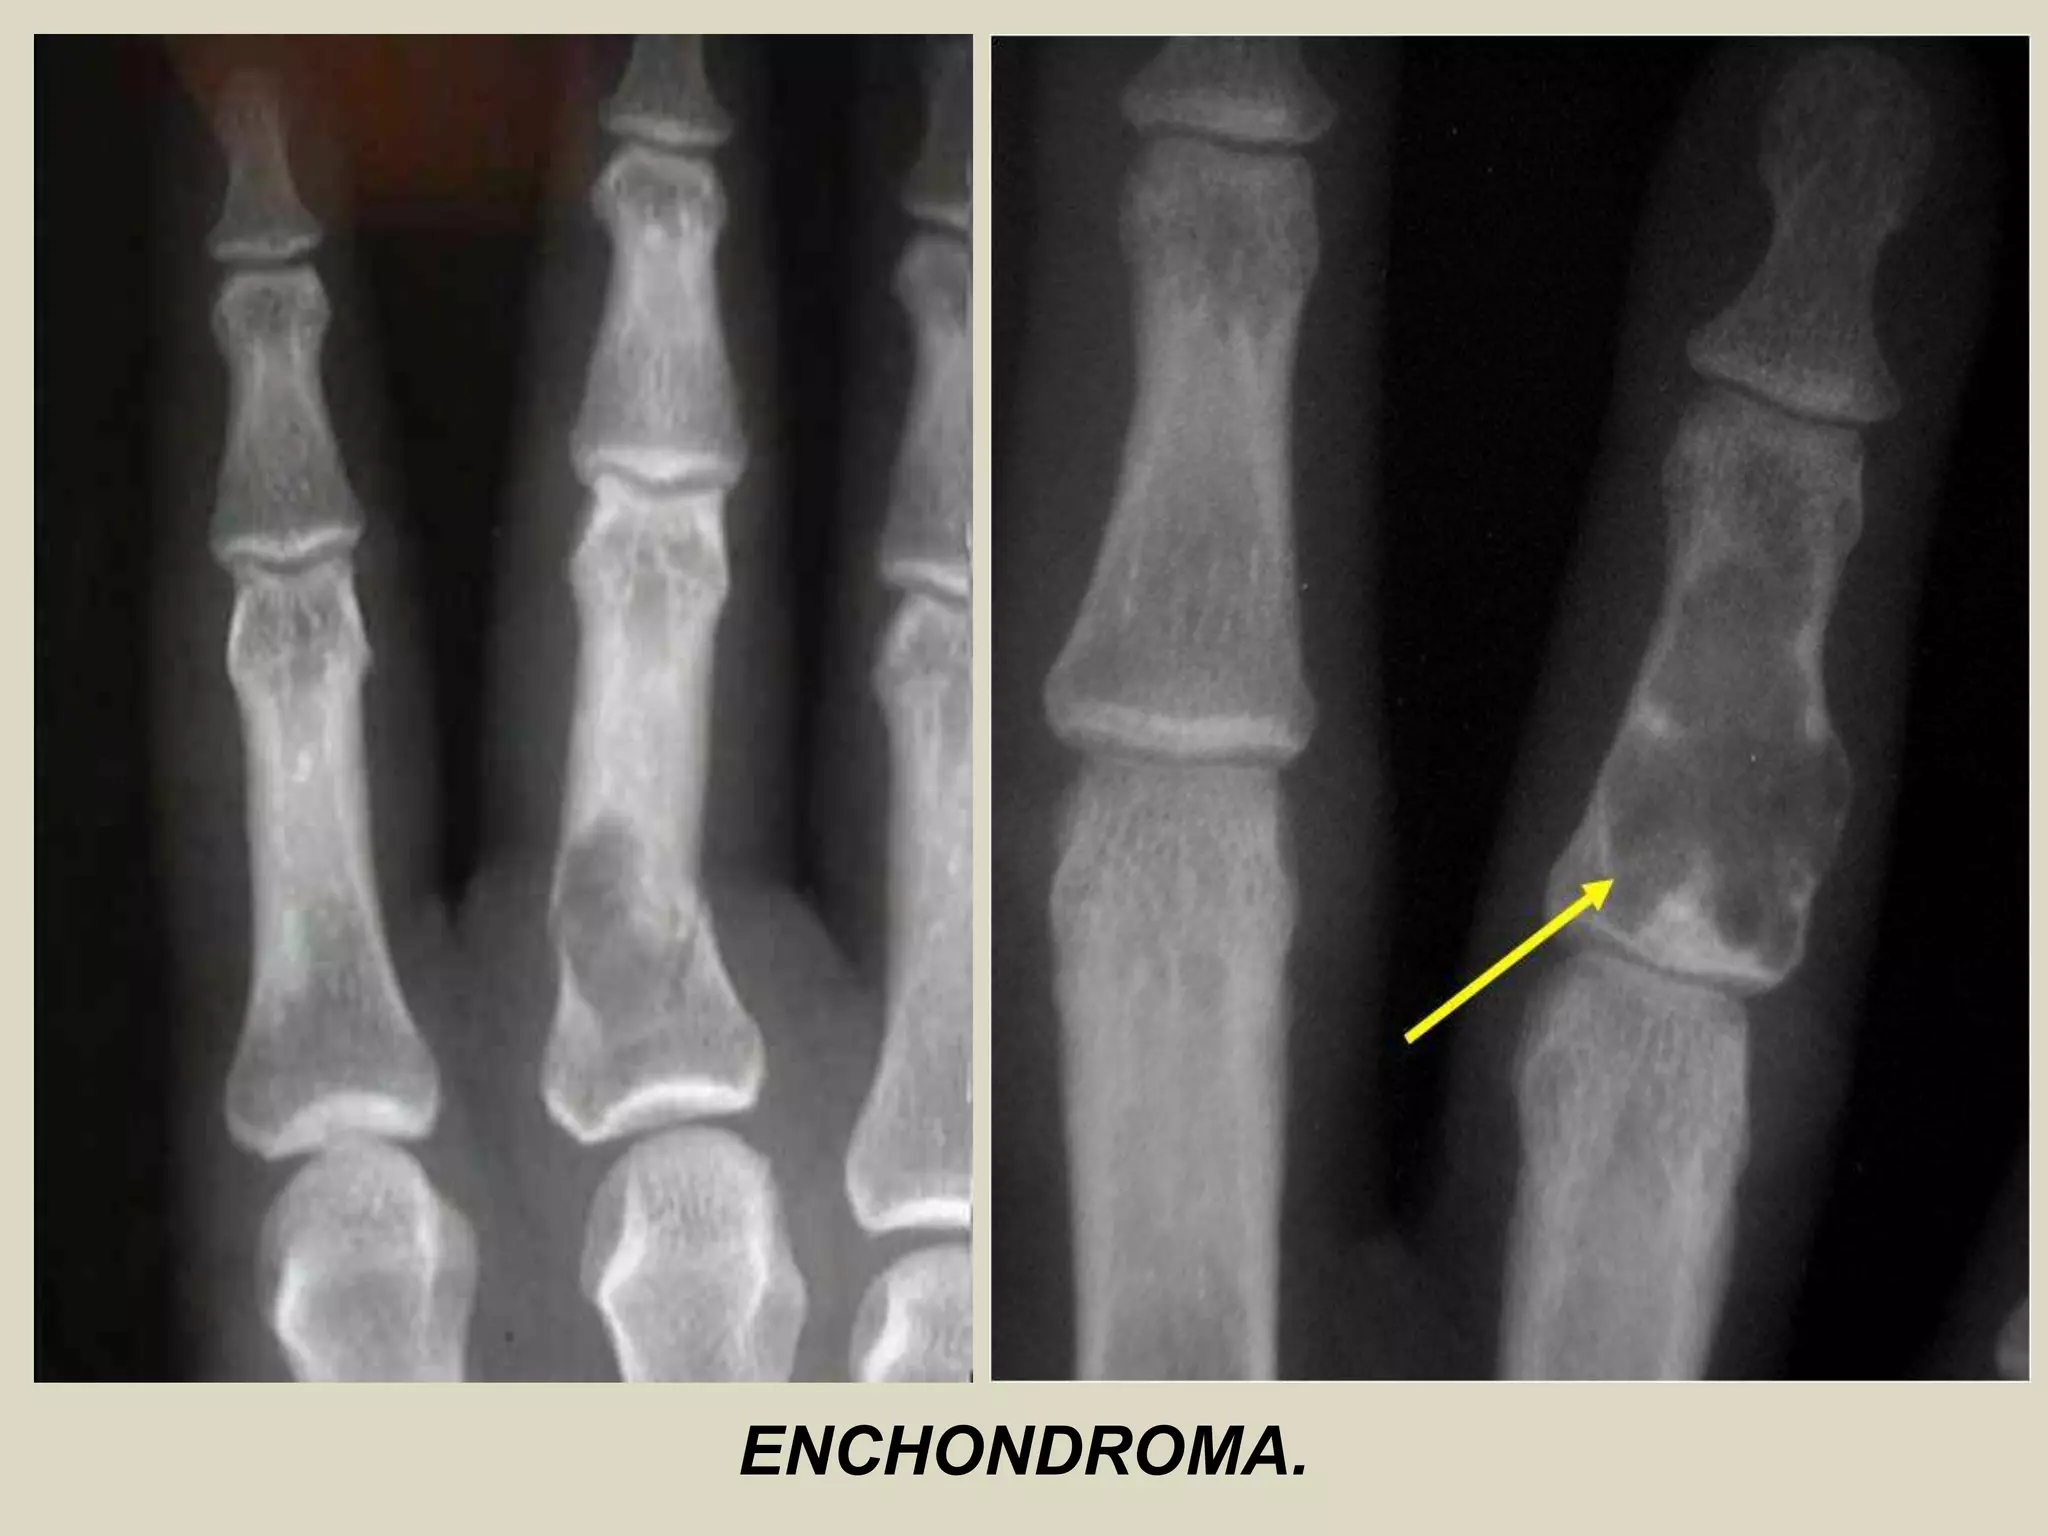

ENCHONDROMA AND ENCHONDROMATOSIS

Definition: Benign hyaline cartilage neoplasm of medullary bone.

- Enchondromatosis, is defined as two or more enchondromas, and occurs in two clinical settings: 90% are

associated with Ollier disease (two or more enchondromas) 10% are seen in Maffucci syndrome

(enchondroma + hemangiomas).

Epidemiology:

- Relatively common, accounting for 10-25% of all benign bone tumors.

- Age distribution is wide, ranging from 5-80 years.

- Majority of patients present within the second through fourth decades of life.

- Solitary enchondromas are rare in young children, whereas multiple enchondromas are encountered more

frequently.

- Sexes are equally affected.

Sites of involvement: Usually metaphyseal-diaphyseal in location and frequently affect the short tubular bones of the hands.

- Followed by bones of the feet and the long tubular bones, especially proximal humerus and proximal and distal femur.

Clinical findings:

- In the small bones of the hands and feet typically present as palpable swellings, with or without pain.

- Because they often expand these small bones and attenuate the cortex, they frequently present with

pathological fractures.

- Long bone tumors are more often asymptomatic, and are detected incidentally in radiographs or bone scans taken

for other reasons.

Imaging:

- Well marginated tumors that vary from radiolucent to heavily mineralized.

- Mineralization pattern is characteristic, consisting of punctate, flocculent, or ring and arc pattern.

- Long bone tumors are usually centrally located within metaphysis.

- Diaphyseal long bone tumors are less common, and epiphyseal tumors are rare.

- Enchondromas in the small tubular bones can be centrally or eccentrically located, and larger tumors may

completely replace medullary cavity.

- More extensive endosteal erosion is considered suspicious for low grade chondrosarcoma.

- Cortical destruction and soft tissue invasion should never be seen in enchondromas and would be most

consistent with chondrosarcoma.

ENCHONDROMA.